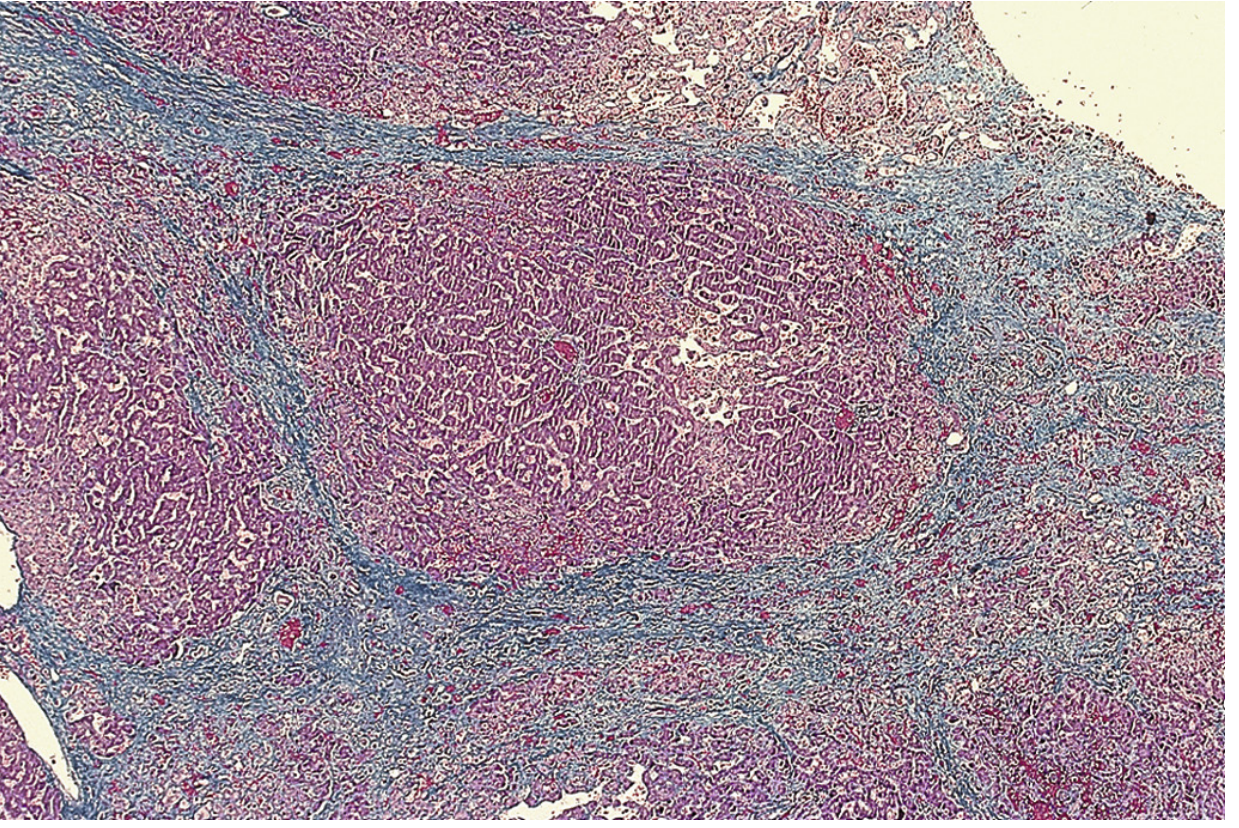

Histology — cardiac cirrhosis (Masson trichrome stain):

Histology of cardiac cirrhosis showing portal tract centered in regenerative nodule with fibrotic bands bridging central veins, dilated congested sinusoids, Masson trichrome stain

Low-power view showing a portal tract at the center of a regenerative nodule, with fibrotic bands bridging central veins. Sinusoids are dilated and congested. No inflammatory cells. (Masson trichrome)Sleisenger and Fordtran's Gastrointestinal and Liver Disease, Fig. 85.10

Histopathology

• Sinusoidal distention and hepatocyte atrophy in centrilobular zones

• Centrilobular necrosis (correlates with recent hypotension episodes)

• Centrilobular fibrosis progressing to bridging fibrosis between central veins (reverse lobulation) → cardiac cirrhosis

• No significant inflammatory infiltrate — "bland" cirrhosis